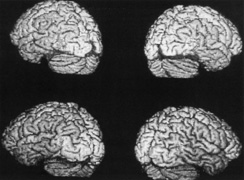

Most striate lesions are infarction, mainly from posterior cerebral artery occlusion (Fig. 14), with sudden onset visual loss and sometimes headache.53 In about half, the visual field defect is the only deficit,53 but in others damage to medial occipito-temporal regions causes amnesia, prosopagnosia, and color perception defects. A syndrome of agitated delirium and hemianopia occurs with lesions of the medial occipital lobe, parahippocampus, and hippocampus.54–56 Brainstem signs include impaired level of consciousness, III nerve palsy, dysarthria and hemiplegia.53 Causes of ischemia are most frequently cardiac emboli and vertebrobasilar occlusive disease; migraine is a rare cause of permanent defects.53 Hemorrhage, vascular malformations, primary and secondary malignancies are much less common.33

Fig. 14. Location and etiology of homonymous hemianopia in 140 patients. (From Fujino T, Kigazawa K, Yamada R: Homonymous hemianopia. A retrospective study of 140 cases. J Neuroophthalmol 6:17, 1986, Aeolus Press, with permission.)